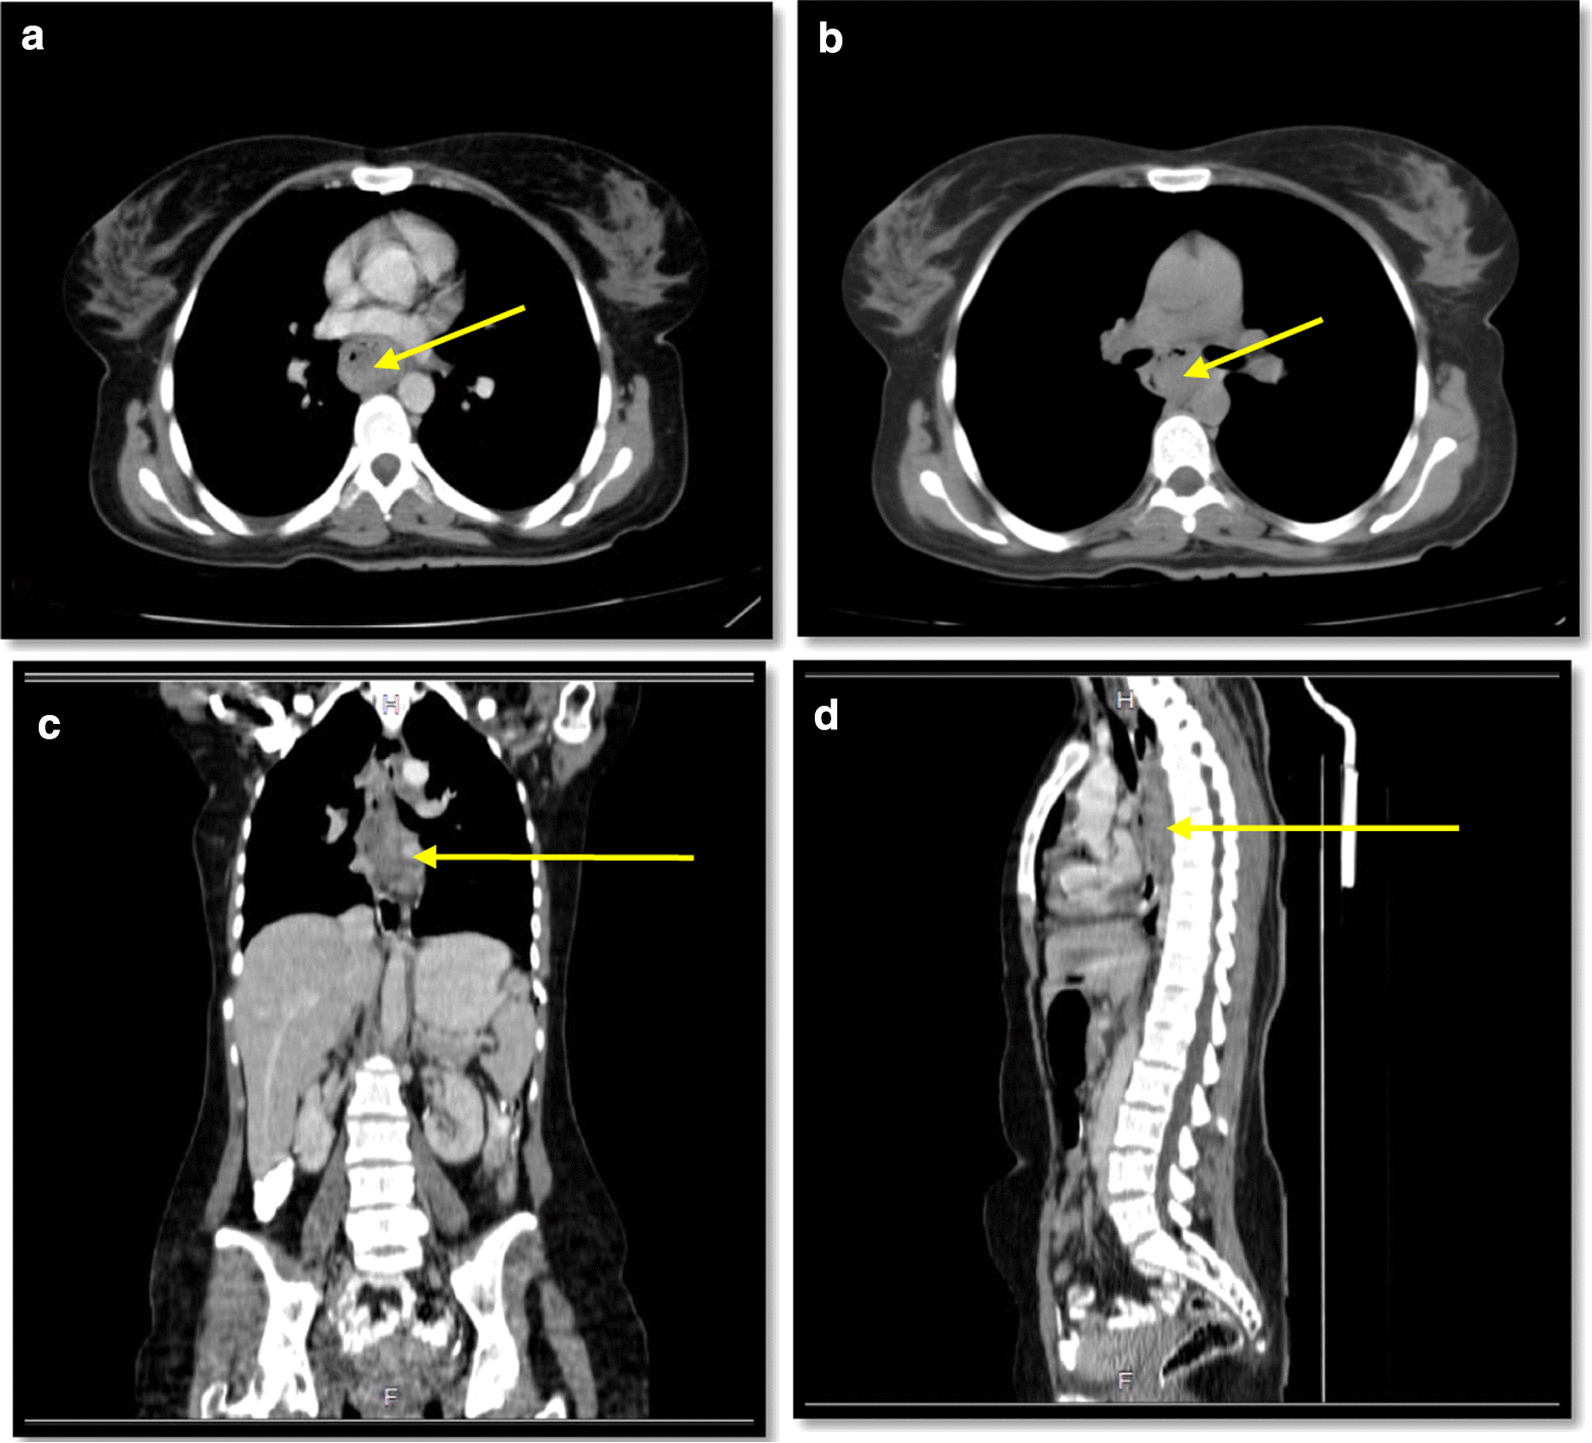

In spiral chest CT scan with and without intravenous (IV) contrast, obtained axial images, represented a 29 × 18 mm soft tissue fullness at middle to distal esophagus (at the level of the carina to the level of the main pulmonary artery), which was suggestive for a tumoral lesion. No lung metastasis was found. In spiral abdomen and pelvic CT scan with oral and IV contrast, there was a 12 × 9 mm LN within gastrohepatic ligament (Fig. 2). In the abdomen and pelvic sonography, there was a 10 × 9 mm hypoechoic lesion between the left liver lobe and greater curvature which was suggestive of lymphadenopathy (LAP) (Fig. 3.).

Fig. 2.

Spiral chest CT scan with and IV contrast (yellow arrows show the tumor); a axial view with IV contrast; b axial view without contrast; c coronal view with IV contrast; d sagittal View with IV contrast